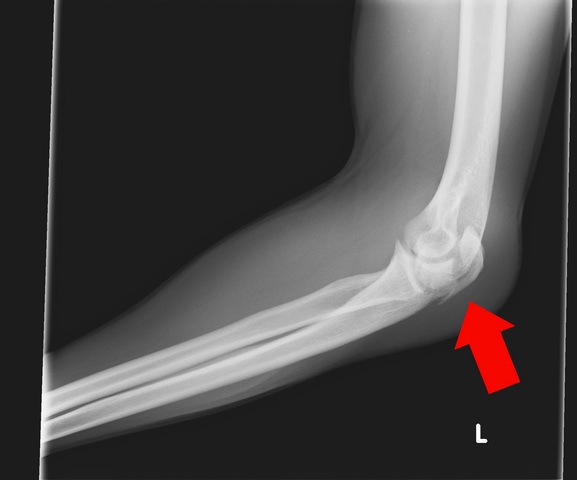

• Broke My Elbow

Broke My Elbow

Going into my first baseball game for horizon I was pumped and ready to go but also very nervous. During pregame warmup my elbow was bugging me, I ended up throwing a baseball in long toss and my elbow popped and my whole arm went numb. I tore my growth plate clean off my left elbow. Thus ending my Baseball career